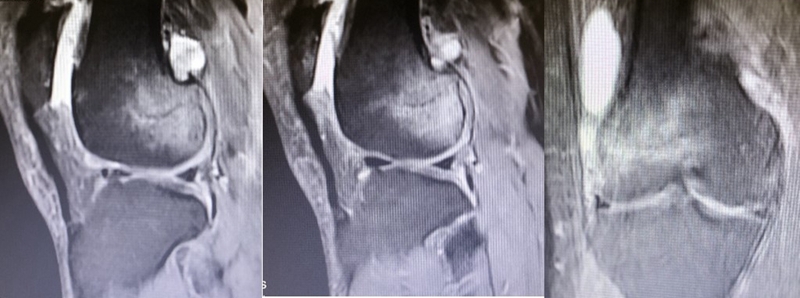

SONK与内侧半月板后根部损伤,有国外学者在SONK患者中通过MRI及关节镜检查,常可发现合并内侧半月板后根部的撕裂,该发生率可达到80%(24/30), 15例完全撕裂,9例部分撕裂。结果表明SONK可能与内侧半月板后根部撕裂后,导致股骨负重区的应力集中、软骨下骨髓水肿有关。

对于半月板损伤类型对SONK的影响,一项研究结果显示内侧半月板后根部撕裂组的半月板突出率为46.1%,平均坏死面积为423.1mm2。内侧半月板后角水平裂组的半月板突出率为35.3%,平均坏死面积为175.8mm2

与内侧半月板后角水平撕裂相比,后根撕裂将导致更大程度的突出和更广泛的骨坏死。

SONK与内侧半月板突出的相关研究中,100%(104)SONK中都有半月板突出,4个SONK在发病前因膝关节疼痛体检发现半月板突出,几个月后通过MRI检查显示存在 SONK。

研究证明半月板挤压是SONK的发病机制之一,半月板挤压的进展可能与SONK的发展有关。